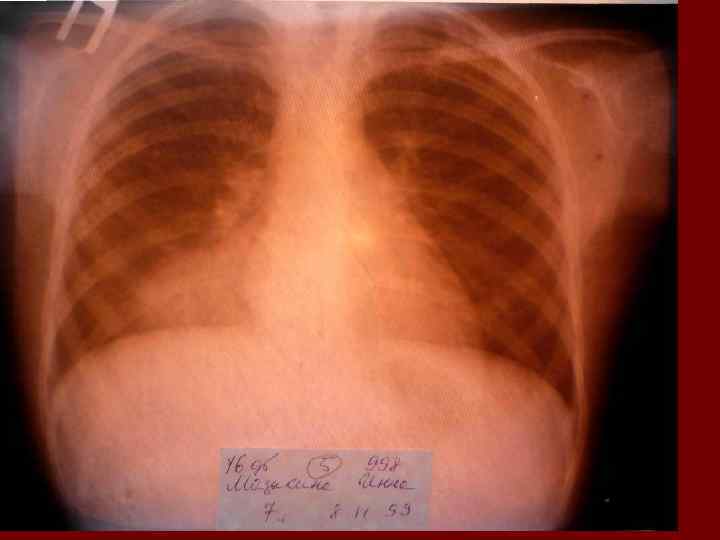

Долевая пневмония характеризуется лобарным пневмоническим инфильтратом. Крупозная ( пневмококковая) пневмония диагностируется прежде всего по клиническим данным. Крупозная пневмония сохраняет свою типичную картину пневмококковой пневмонии: острое начало с характерными клиническими данными, циклическое течение, несклонность к деструкции, гомогенной и лобарной инфильтративной тенью при рентгенологическом исследовании. Вместе с тем, широкое использование антибиотиков способствовало значительному снижению числа крупозных пневмоний у детей. Интерстициальная – редкая форма пневмоний, при которой оказывается поражен прежде всего интерстиций. Как правило, интерстициальная пневмония обусловлена вирусами, пневмоцистами, внутриклеточными микроорганизмами и грибами.

Морфологическую форму пневмонии определяют по клинико – рентгенологическим данным: выделяют очаговую, очагово – сливную, долевую ( крупозную), сегментарную и интерстициальную пневмонии. Очаговая – наиболее распространенная форма. Пневмонические очаги чаще бывают размером 1 см и более. Очагово – сливная – инфильтративные изменения в нескольких сегментах или во всей доле легкого, на фоне которых могут быть видны более плотные участки инфильтрации и/или полости деструкции. Сегментарная – в процесс вовлекается весь сегмент, который, как правило, находится в состоянии гиповентиляции, ателектаза. Морфологическая картина воспаления при очаговых и сегментарных пневмониях связана с первичным инфекционным воспалением в бронхах, что дает основание отнести эти варианты поражения легочной ткани к бронхопневмониям, нередко сопровождающихся бронхообструктивным или бронхообтурационным синдромами. В настоящее время данный тип пневмоний у детей встречается наиболее часто.